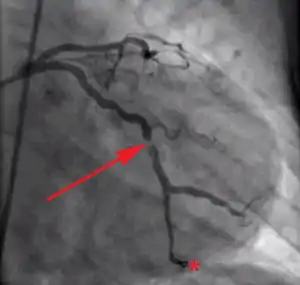

Coronary angiography of a patient with a heart attack.